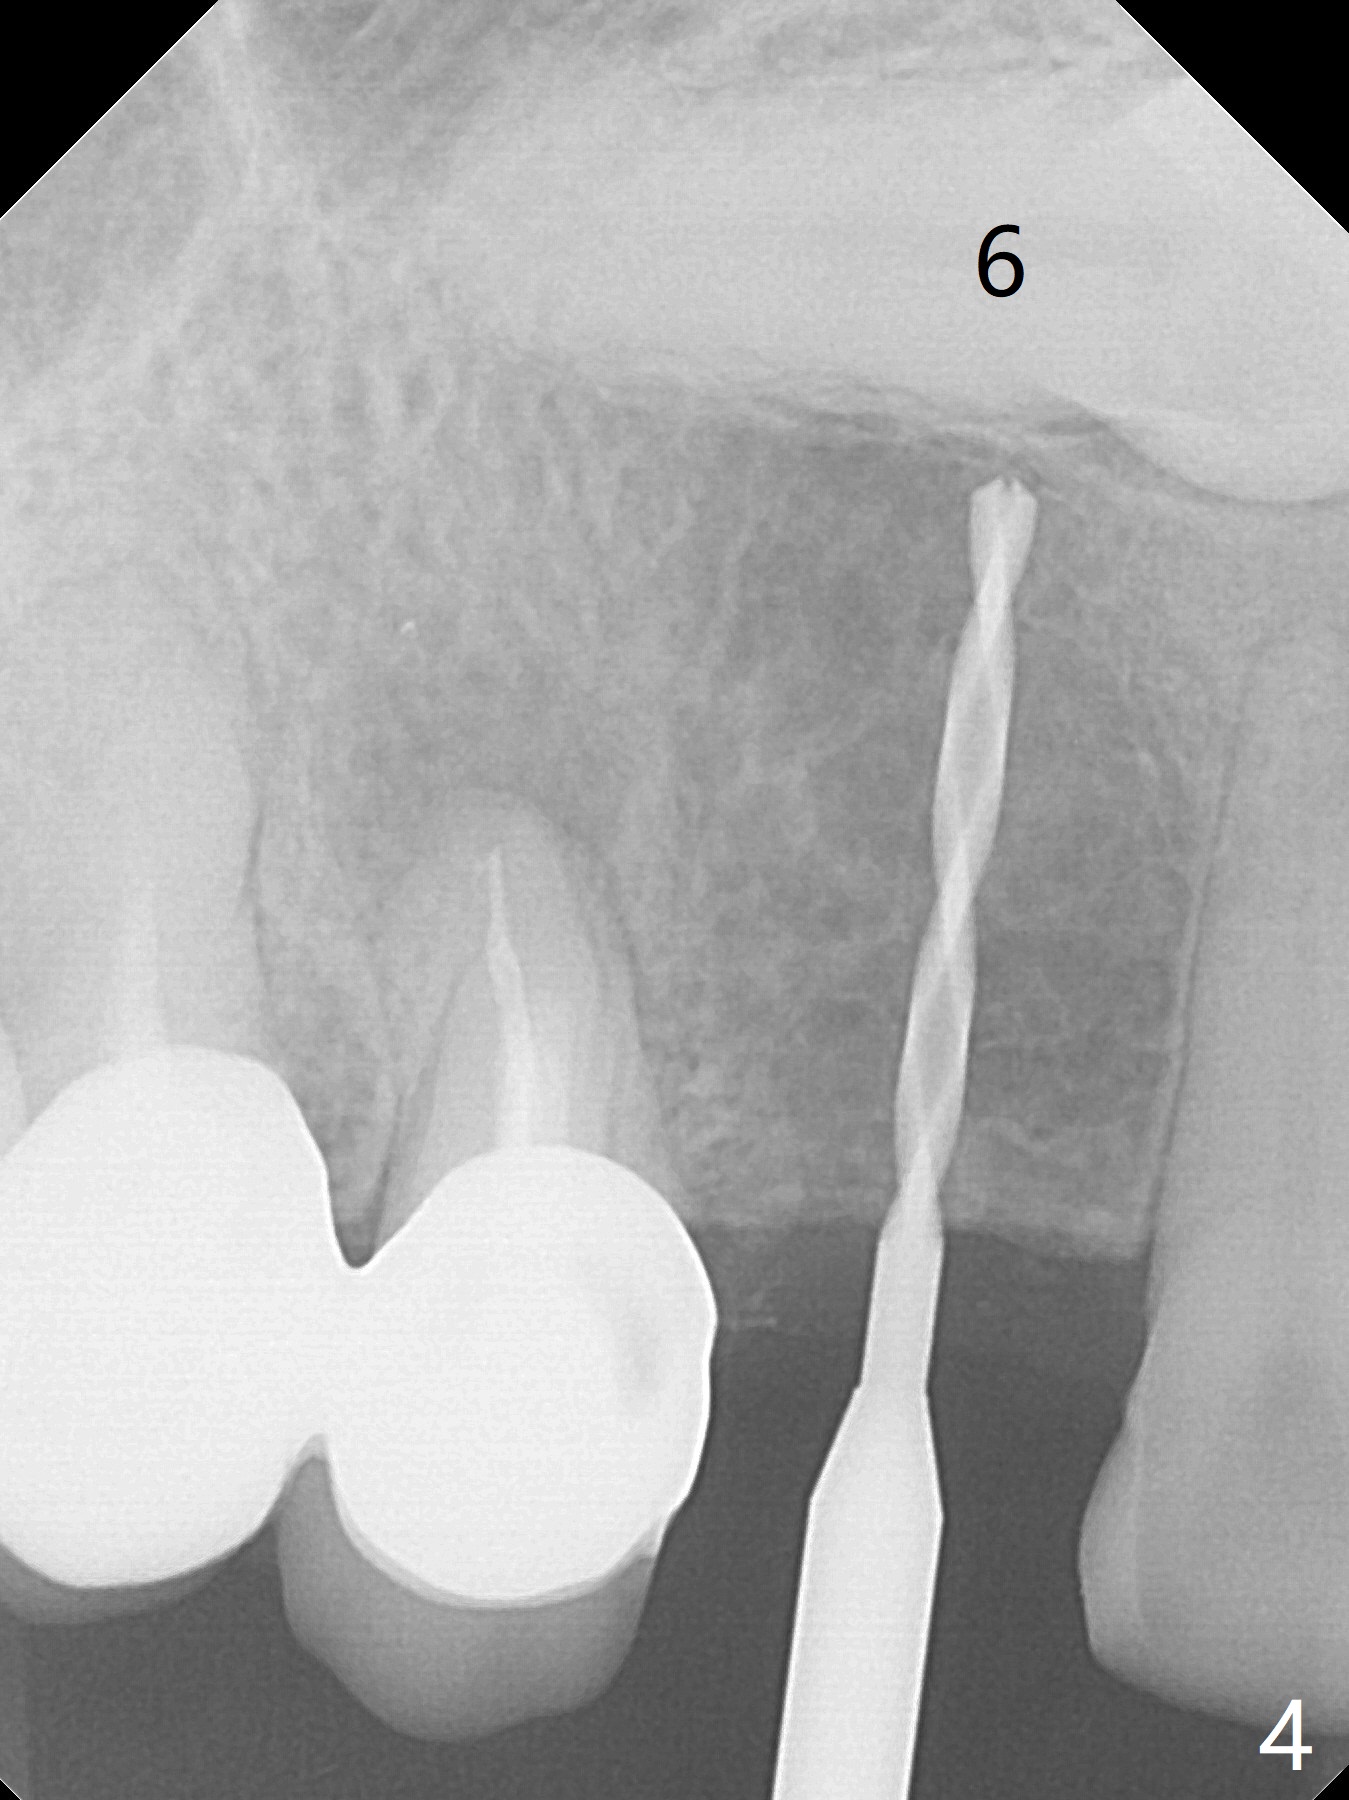

After removal the pontic of a cantilever FPD (Fig.1), a residual root is found at #6 with the buccal concavity (Fig.2 *). The ridge is narrow with flap elevation (Fig.3). PA taken with a 1.2 mm drill for 14 mm shows a horizontally impacted canine (Fig.4: #6). When the osteotomy is finished without apparently buccal perforation (Fig.5), the trajectory is buccal. When a 3x14 mm (12.5 mm in bone) 15 degree angled 1-piece implant is placed with normal trajectory (Fig.6), the buccal plate is perforated. As the implant is redirected so that the apical end of the implant does not stick out buccally, the trajectory returns buccal (Fig.7). The buccal aspect of the abutment is heavily reduced for an immediate provisional. The perforation is repaired with Vanilla Graft and Collagen Dressing before suturing. CT should have been taken preoperatively; the osteotomy should have been initiated as palatal as possible, as compared to that in Fig.5. When the 1st drill is used. it should be checked for restoration. An angled abutment does not help the trajectory substantially. The implant is loose 1.5 months (partially due to mastication); after retightening, CT is taken (Fig.8). The implant is within the bone. If the implant becomes loose again, extract the impacted canine and place the longest implant (22 mm) palatally. The implant is stable nearly 4.5 months postop (Fig.9). The patient is not satisfied with buccally-placed crown. The implant is removed with bone graft 6 months postop.